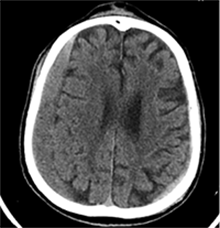

53 m. vyras sumuštas gatvėje ir greitosios medicinos pagalbos atvežtas į Priėmimo skyrių. Pacientui atlikta galvos kompiuterinė tomografija (GKT). Rasta: poūmė, stora, apie 16 mm dydžio subdurinė hematoma (SDH) dešinėje pusėje konveksitaliai ir ūmi nedidelė SDH kairėje pusėje frontoparietaliai. Vidurio struktūrų dislokacija (VSD) į kairę – minimali. Kairėje – kaukolės skliauto linijinis lūžis. Nustatyta nosies kaulų, nosies pertvaros, dešiniojo viršutinio žandikaulio kaktinės ataugos ir kūno, sinuso sienelių lūžių, dešinės akiduobės medialinio krašto lūžių ir dešiniojo skruostinio lanko lūžių (1 pav.). 2020 m. liepos mėn. pacientas skubos tvarka operuotas: atlikta dešinė kraniotomija, pašalinta hematoma. Atlikus kontrolinę GKT, buvo matyti, kad pašalinta didžioji hematomos dalis (2 pav.). Pacientas konsultuotas veido ir žandikaulio chirurgo, skubus chirurginis gydymas neindikuotas. Praėjus 3 savaitėms, pacientas, esant gerai funkcinei ir neurologinei būklei, tolesnio gydymo perkeltas į slaugos ligoninę, vėliau išleistas gydytis ambulatoriškai.

2 pav. Po pirmosios operacijos (didžioji hematomos dalis pašalinta, VSD be dislokacijos)